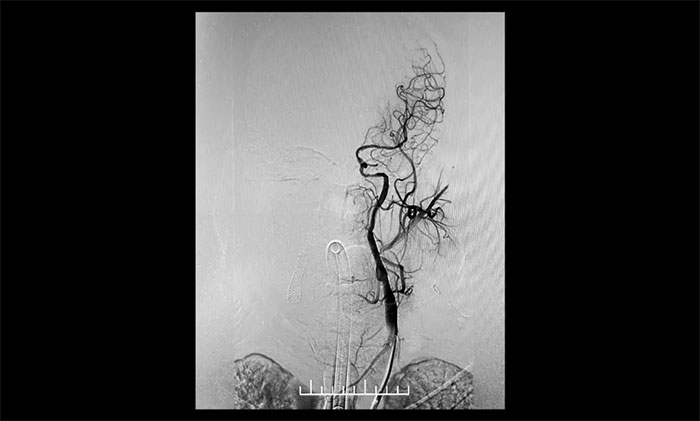

患者为老年男性,因言语不利,伴右侧肢体活动不利入院。外院行头颅CT检查:双侧脑室旁及基底节区腔隙灶。入院后,头颅MRI平扫+DWI+MRA提示,脑干、双侧小脑及双侧大脑半球多发腔梗、缺血灶;MRA:脑动脉硬化,左侧颈内动脉不完全闭塞,右侧颈内动脉C3-C6段、右侧大脑中动脉M2段多发狭窄。“主动脉弓+全脑动脉造影”提示:右颈内动脉起始段重度狭窄,左颈内动脉起始段重度狭窄,串联左颈内动脉岩骨段中度狭窄,左颈内动脉眼动脉段闭塞。

▲ 右颈内动脉起始段重度狭窄